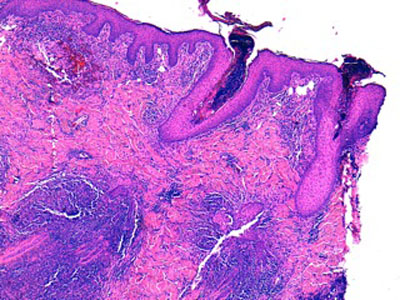

Histologie : L ‘épiderme et les infundibula folliculaires sont hyperplasiques, sièges d’une acanthose régulière d’intensité modérée, associée à une hyperpigmentation et à une hyperkératose tantôt orthokératosique, tantôt focalement parakératosique d’intensité modérée. La couche cornée est ainsi épaissie, croûteuse, stratifiée. L’épiderme et les structures infundibulaires, sont le siège d’une régulière exocytose de petits lymphocytes et plus rarement de neutrophiles. Dans le derme, les sacs folliculaires sont rarement rompus et les glandes sudorales font l’objet de remaniements inflammatoires chroniques, plasmocytaires. Au sein de la kératine libre péri-pilaire et au sein de la couche cornée de l’épiderme, on observe de rares hyphes mycéliennes PAS positives.

dermatophytose-atypiqueh3-jpegEFH3

Ce chien présente donc des lésions de mycose superficielle à filaments très kératinophiles associée à des lésions de pyodermite profonde

Mycologie : la mycologie réalisée à l’ENVA permettra l’identification d’un Microsporum canis